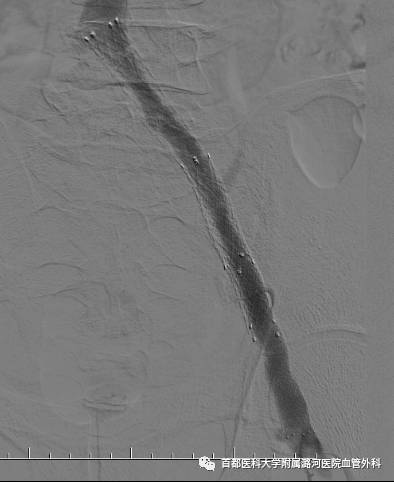

下肢CTV

下肢静脉CTV:

下腹部平扫也能初步判断有没有左髂静脉压迫,对于怀疑该疾病的可以常规检查下腹平扫CT。